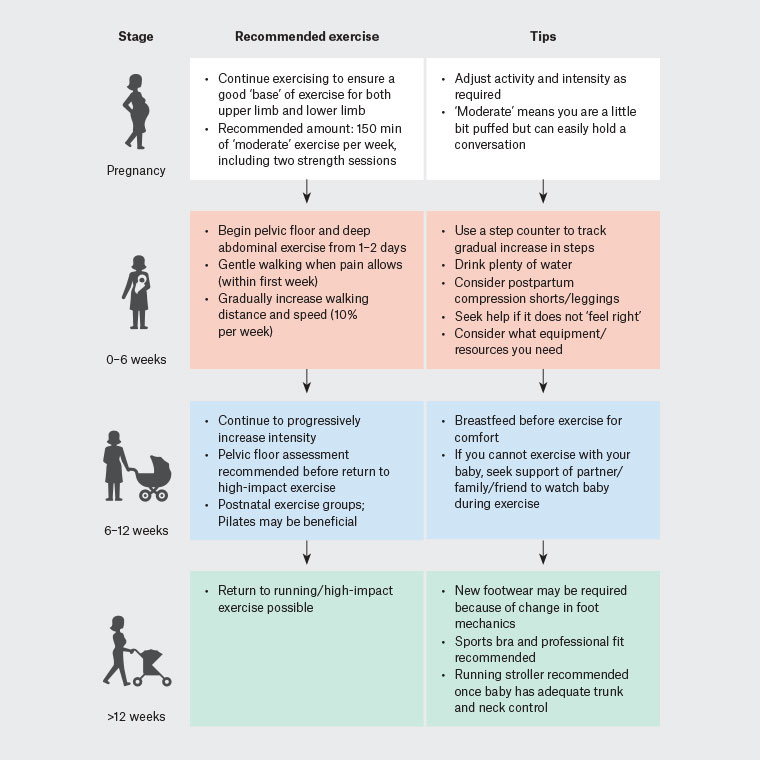

What kinds of exercise will be helpful for pelvic floor recovery?

(Source : Return to exercise post pregnancy, Philipp Inge Jessica J Orchard Rosie Purdue John W Orchard, 2022), doi: 10.31128/AJGP-09-21-6181

Link :Exercise after pregnancy (RACGP)

https://www1.racgp.org.au/ajgp/2022/march/exercise-after-pregnancy